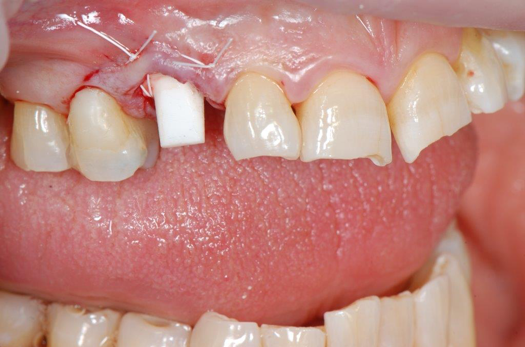

Fig 6. After splint removal (12 weeks postoperatively).

Figure 6

Fig 7. 12 weeks postoperatively.

Figure 7

Figure 3 through Figure 5 show the fitting of a one-piece multiple splint using a light-cured acrylic, along with flowable composite to adhere the splint to the three ceramic dental implants. The splint was to remain out of occlusion, without any occlusal forces for the 12-week osseointegration period. The patient was instructed to chew on the other side of her mouth for the 12 weeks before returning to the dental practice for simple removal of the splint. Removal of the splint revealed optimum results. The soft tissues were pink, with keratinized gingival margins completely surrounding the ceramic implants and consistent with what most dentists observe with the periodontium around periodontally healthy natural teeth (Figure 6 and Figure 7).